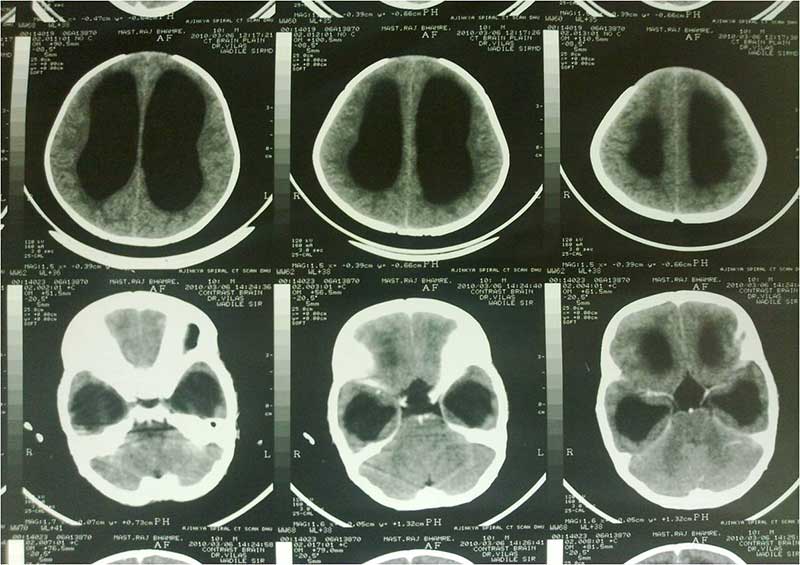

Pre OP CT

PRE OP CT 2